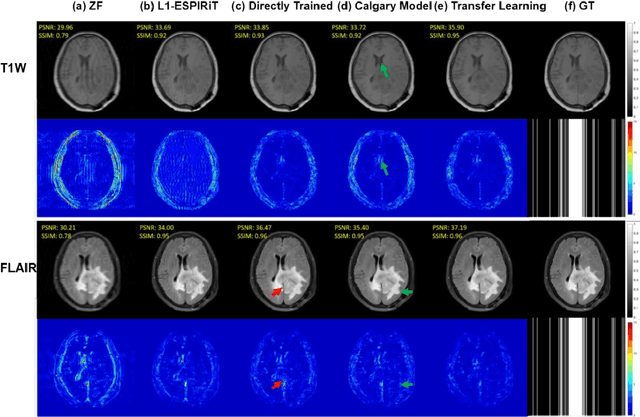

Abstract:Deep learning based generative adversarial networks (GAN) can effectively perform image reconstruction with under-sampled MR data. In general, a large number of training samples are required to improve the reconstruction performance of a certain model. However, in real clinical applications, it is difficult to obtain tens of thousands of raw patient data to train the model since saving k-space data is not in the routine clinical flow. Therefore, enhancing the generalizability of a network based on small samples is urgently needed. In this study, three novel applications were explored based on parallel imaging combined with the GAN model (PI-GAN) and transfer learning. The model was pre-trained with public Calgary brain images and then fine-tuned for use in (1) patients with tumors in our center; (2) different anatomies, including knee and liver; (3) different k-space sampling masks with acceleration factors (AFs) of 2 and 6. As for the brain tumor dataset, the transfer learning results could remove the artifacts found in PI-GAN and yield smoother brain edges. The transfer learning results for the knee and liver were superior to those of the PI-GAN model trained with its own dataset using a smaller number of training cases. However, the learning procedure converged more slowly in the knee datasets compared to the learning in the brain tumor datasets. The reconstruction performance was improved by transfer learning both in the models with AFs of 2 and 6. Of these two models, the one with AF=2 showed better results. The results also showed that transfer learning with the pre-trained model could solve the problem of inconsistency between the training and test datasets and facilitate generalization to unseen data.